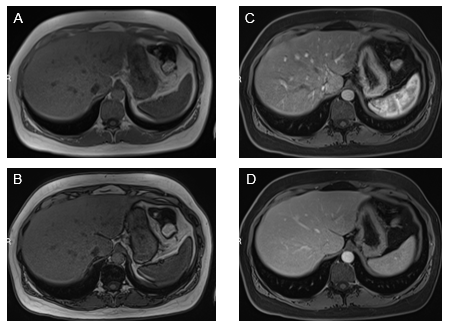

Stomach: The antral region of the stomach is the gastric portion that most commonly shows findings of inflammation (Figure 2). Increased enhancement in the arterial and venous phases is not uncommon. In the gastric portion, submucosal sparing or edema is commonly observed as a thin strip that lacks enhancement. Diffuse gastric enhancement can also be appreciated. Usually, this confers a more serious inflammatory condition of the stomach, such as moderately severe disease.

Figure 2 Axial T1-weighted GRE images. In-phase (A) and out-of-phase (B), show minimal signal drop of the liver on out-of-phase images consistent with mild steatosis. Increased mural enhancement of the stomach is better perceived in the arterial phase images (C).